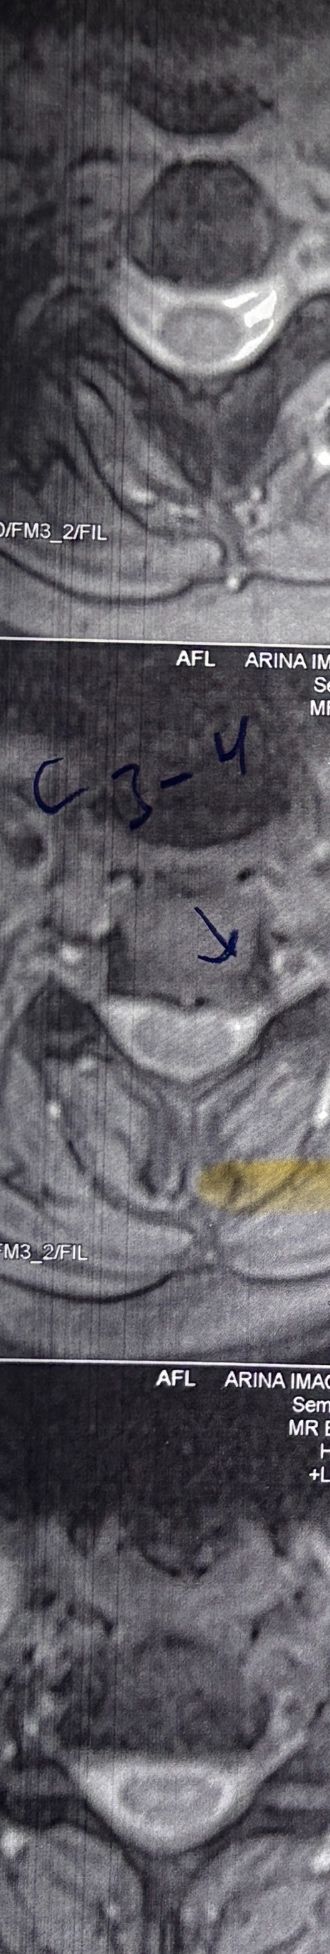

In cervical mri I marked some findings plus their reports